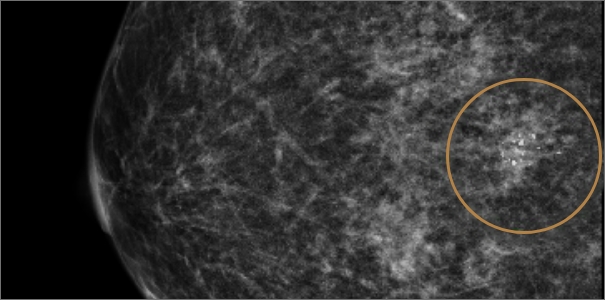

미세석회화

미세석회화란 몸 안에 쌓인 칼슘 성분의 석회질을 뜻합니다.

유방촬영 시 하얀 점으로 보이며 노화, 유선 내 분비물 침착, 염증 등으로 생길 수 있습니다.

대부분의 경우 양성 석회화로 인체에 무해하지만, 유방암으로 인해 생기는 악성 석회화가 의심될 시

조기 발견과 치료를 위해 반드시 조직검사를 통한 악성 여부 확인이 필요합니다.

과거 여러 번 유방촬영을 진행하였지만 진단하기 어려운 치밀유방으로 인해 정상 판정을 받다가

진공흡인 보조장치(맘모톰)의 특수바늘을 통해 병변 확인해 보니

우측 유방 윗부분에 미세 석회가 발견되어조직 채취 후 암 진단 판정되어 치료 진행

치밀유방 여성, 우측 미세석회 발견

진공흡인 보조장치(맘모톰) 조직 채취 후

암 진단 판정